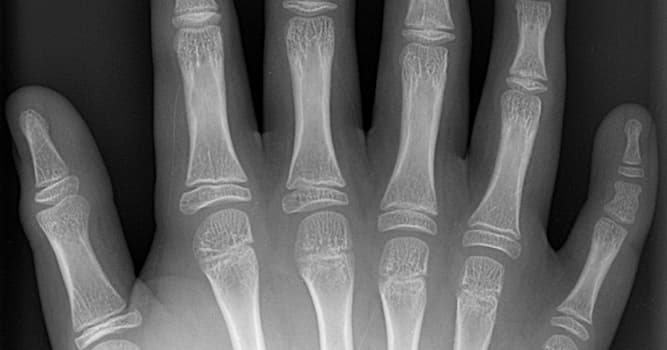

Bij welk orgaan leidt een teveel aan exemplaren tot polydactylie?